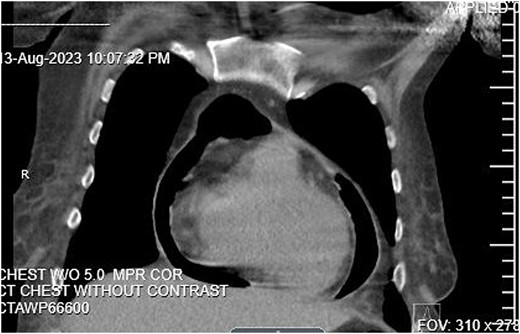

As a part of her workup, it was noted that she had elevated liver function tests, which prompted an abdominal ultrasound that revealed a partially thrombosed portal vein. A follow-up CT of the abdomen and pelvis was then completed. During this CT, the base of the heart was shown to have evidence of pneumopericardium, which led to a CT chest confirming the diagnosis of pneumopericardium with evidence of tamponade (Fig. 1). Tamponade was determined to be primarily contributing to the patient’s hypotension and shock.

CT Abdomen pelvis showing moderate pneumopericardium observable from lower thorax.